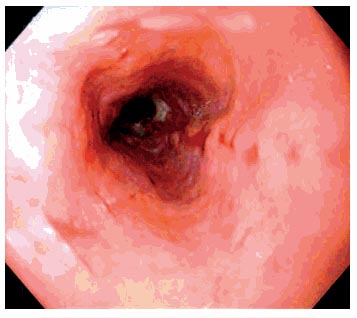

Grade I: Yemek borusunda hafif bir kızarıklık saptanır